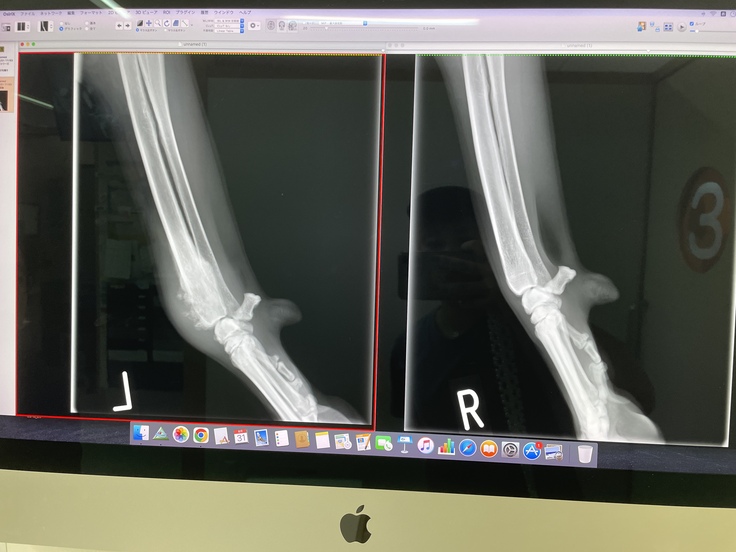

1週間後、家から車で1時間半、紹介して頂いた病院。レントゲン検査の末。

「左前脚の骨肉腫です。」

関節炎とか、骨折と言ってあげれれば良かったんだけど、と。

あぁ、やっぱり、、、と言葉が出ませんでした。

(左側のモヤモヤしている所が骨が融解してサンバーストと言われる所見が見られるところだそうです)

それでも私達は5歳という年齢も考え、モカの残りの人生を自分の脚で歩いて生活が出来る可能性に賭けたいと思い、サルベージ手術をお願いし、9月20日にサルベージ手術を無事に終える事ができました。

(左側が術後のレントゲンです。)